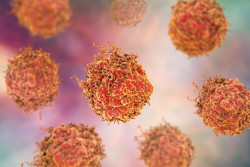

El consumo de té verde y café reduce el riesgo de nuevos eventos cardiovasculares tras un primer infarto o un ictus

Los supervivientes de accidentes cerebrovasculares y ataques cardíacos pueden reducir múltiples causas de muerte y prevenir más eventos cardiovasculares al beber té verde, según una nueva investigación, que también ha encontrado beneficios para estos pacientes y personas sanas cuando se consume diariamente café.